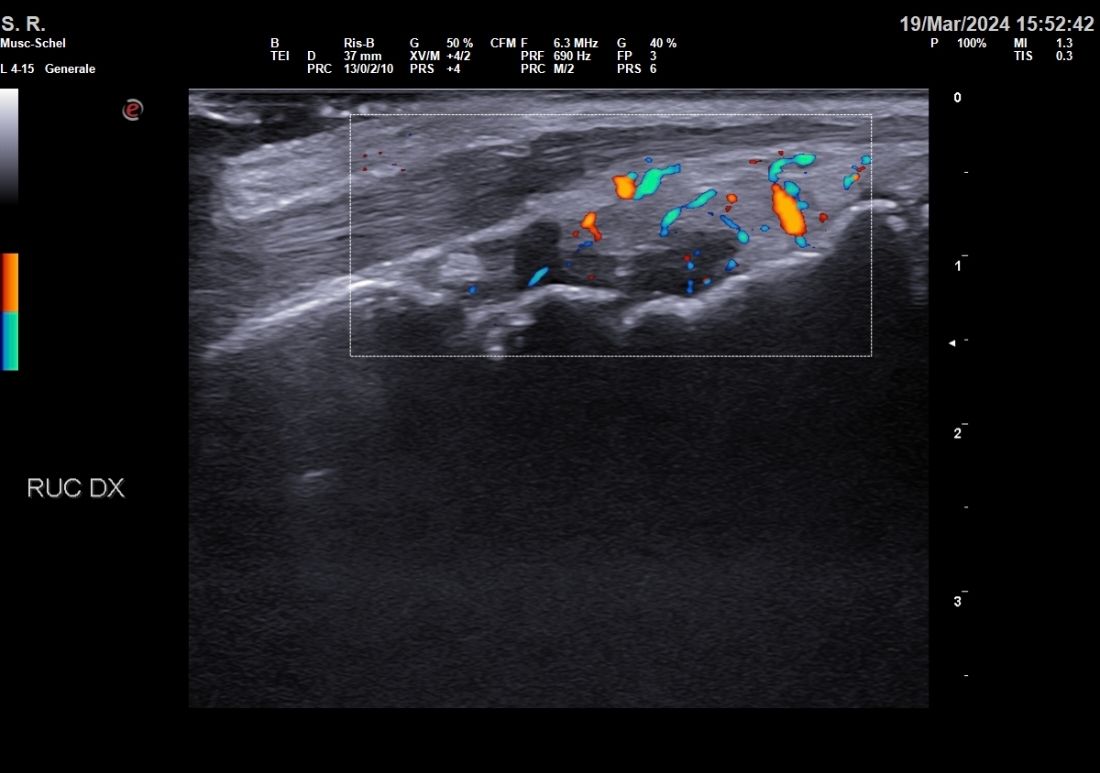

Nel mio percorso formativo ho conseguito esperienza nell'ecograifa articolare, nelle infiltrazioni articolari, nelle biopsie sinoviali e nella gestione delle terapie immunosoppressive con farmaci biotecnologici

• Ecografia osteoarticolare

67 € - 180 €